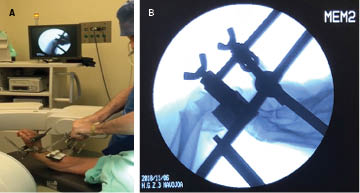

Clinical radiological evaluation of the use of a new device for the closed reduction of distal radio fractures

Distal radius fractures are frequent and represent 55% of the total in children and adults as well as 1.5% of the total emergency room visits. In children, 90% are managed with closed reduction and application of plaster; in adults, treatment varies according to type, experience of the doctor and general condition of the patient. In this setting, it is common for primary care to be delayed due to empirical events, causing significant inflammation and edema, which makes the closed reduction of the fracture difficult, causing the need for open reduction. The present work shows a steel device, designed for the closed reduction of distal radius fractures that was used in public hospitals in Navojoa, Sonora, Mexico. Thirty patients with displaced distal radius fracture with an evolution between one and seven days, from 2017 to 2019, were documented. Standard radiological measurements were performed before and after reduction, obtaining results of 96.66% of the cases with satisfactory alignment, and statistically significant difference between pre and post indices (p < 0.05). One case required surgical treatment for poor correction, no distal neurovascular complications caused by the reduction mechanism were documented. Biomechanical tests were performed on the device that showed advantages over the traditional thumb reduction technique. It is concluded that this device for the closed reduction of distal radius fractures is an effective tool and that it is possible to favor its use.

Figure 2